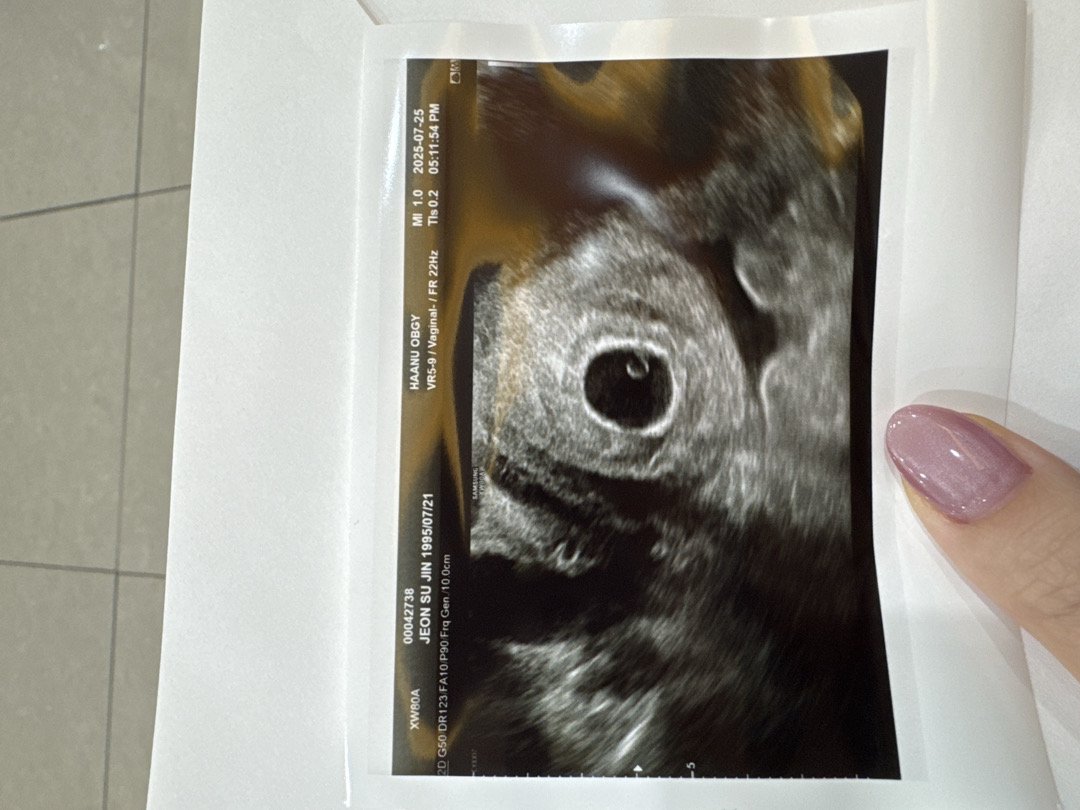

아기가 보이실까요..?

난황밑에 ㅁ뭔가 있는거 같은데 뭐로 보이세요..?

아직 안보인다고는 하셧어요!!